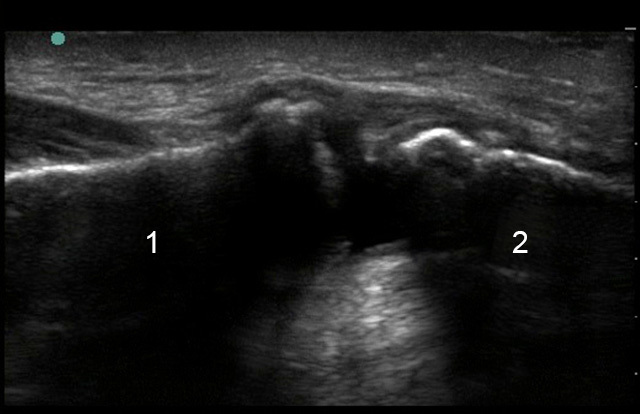

Shoulder Acromioclavicular (AC) Joint Separation Image

Clavicle

Acromion